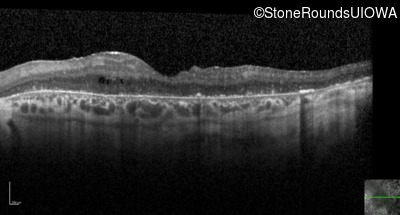

Optical Coherence Tomography - Right - 20/250 sc

Exemplar / OCT Stack

OCT Stack